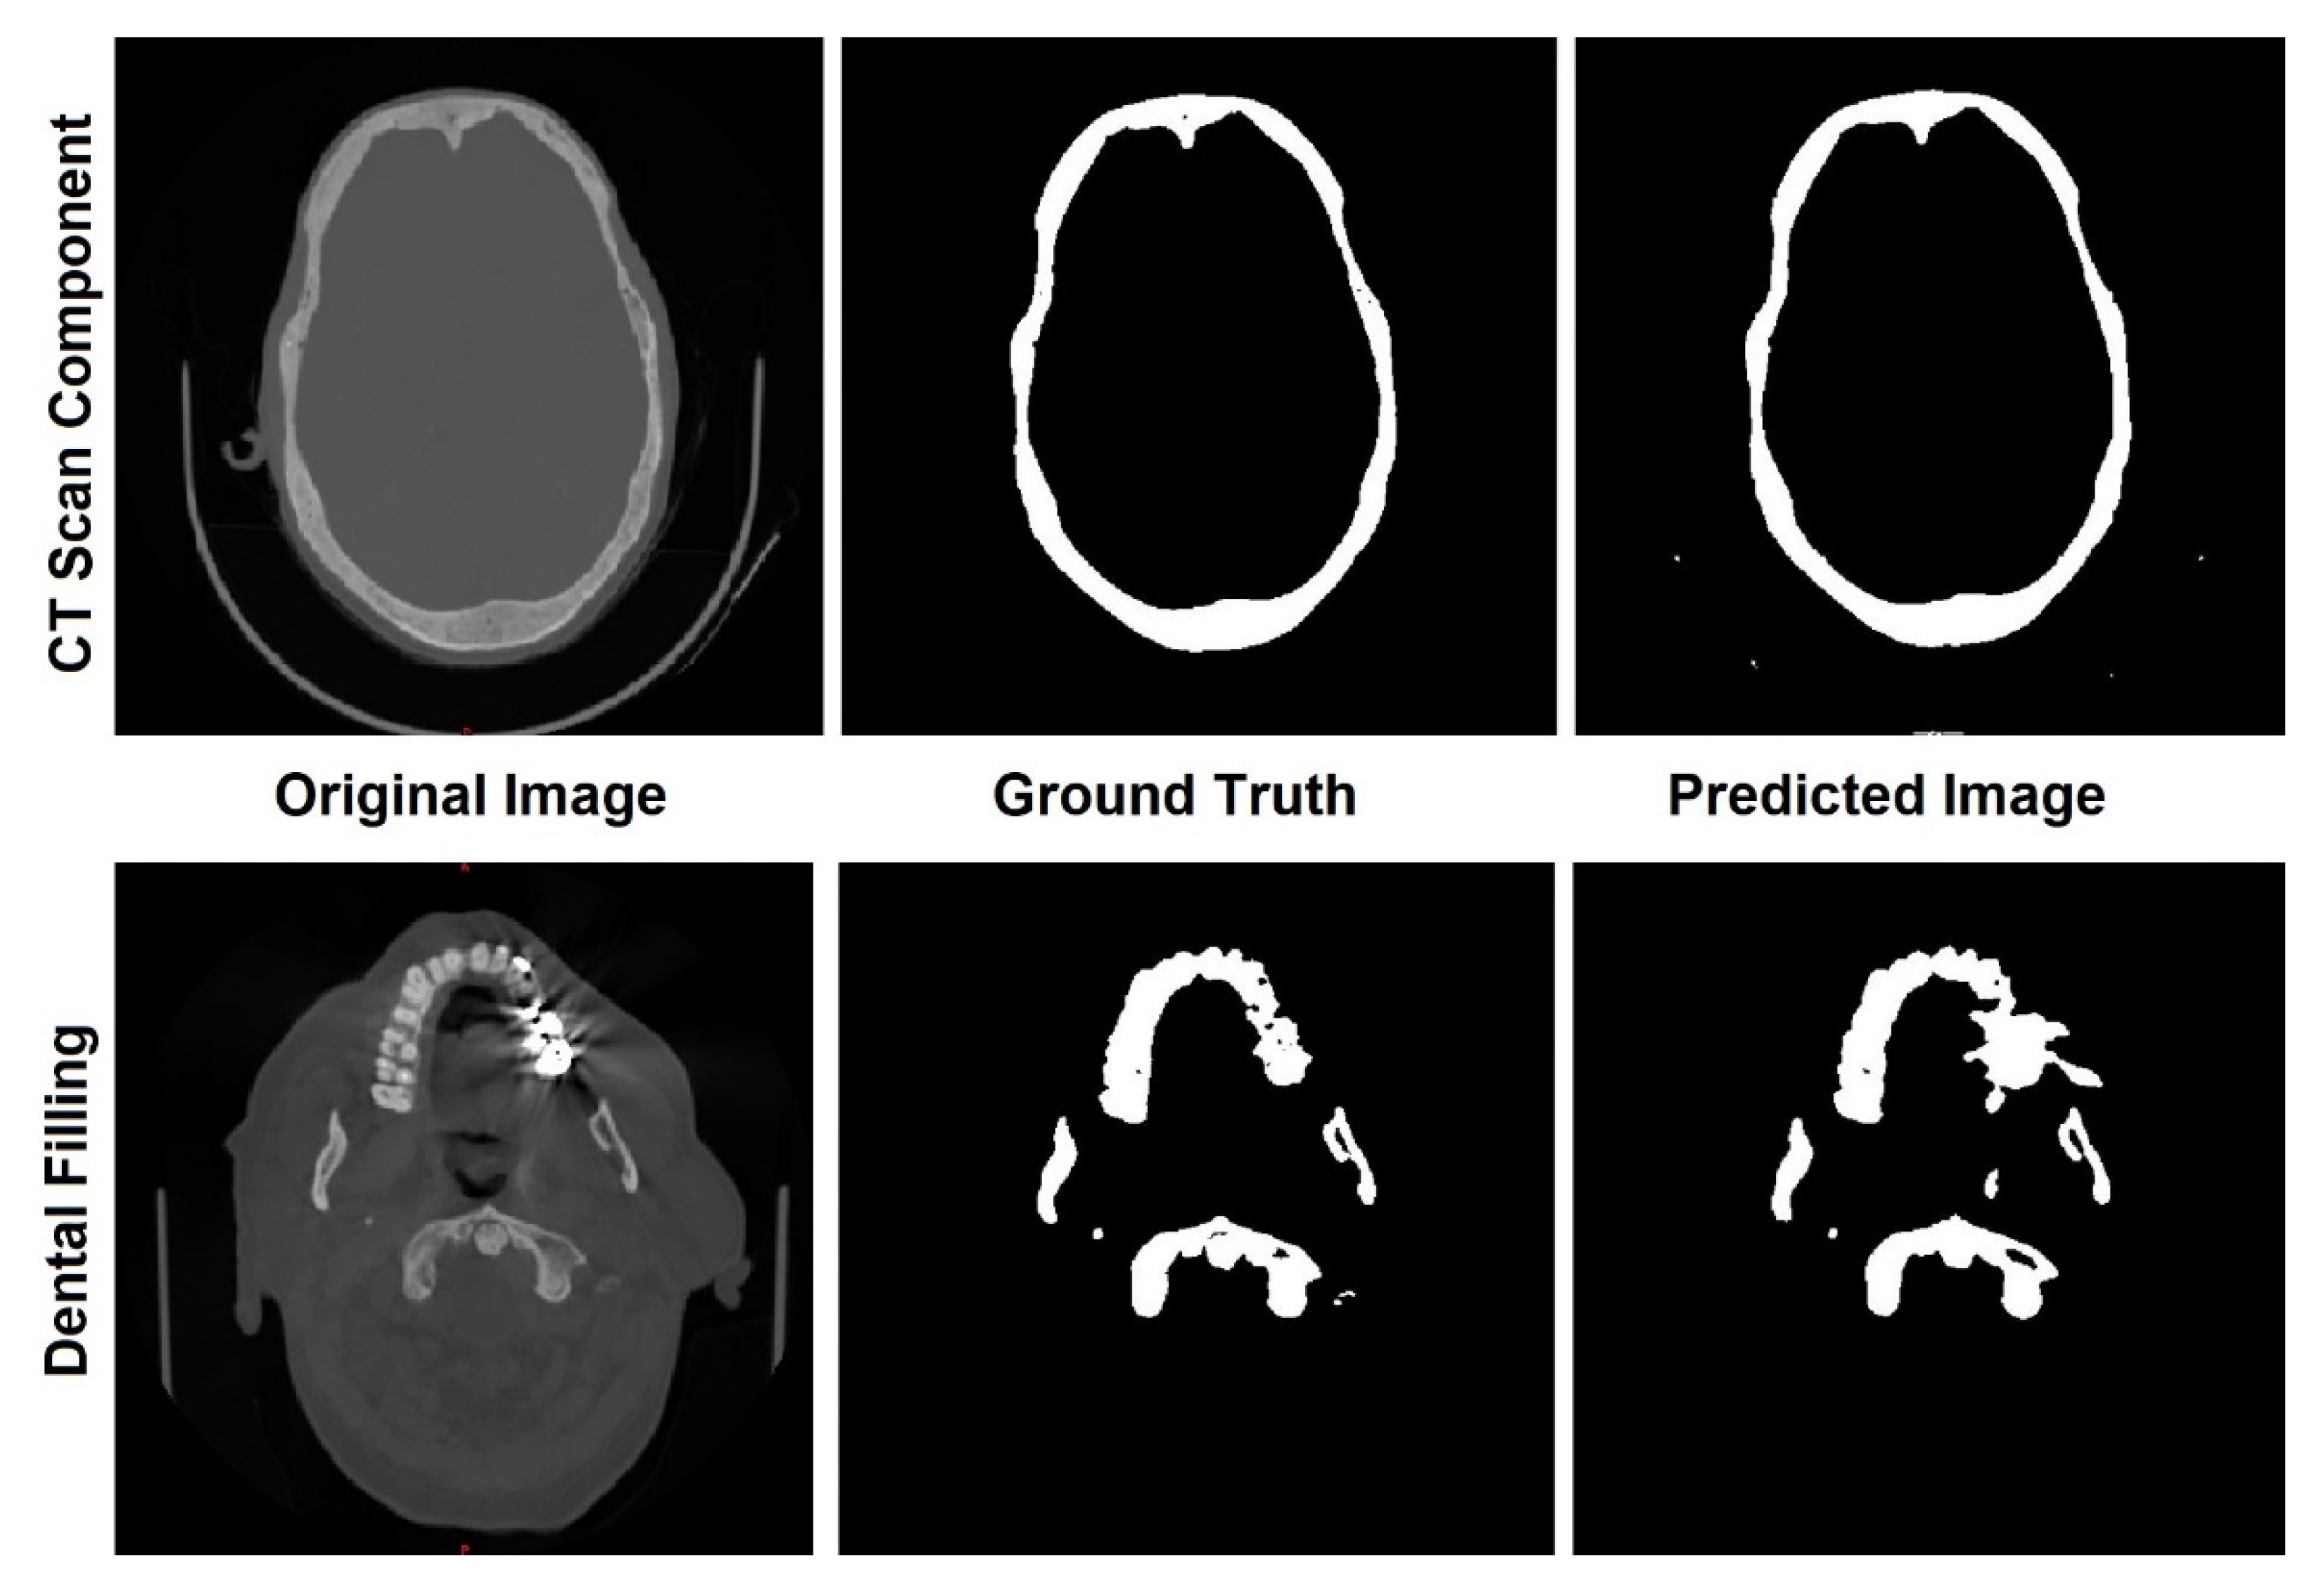

3.1. Skull Segmentation